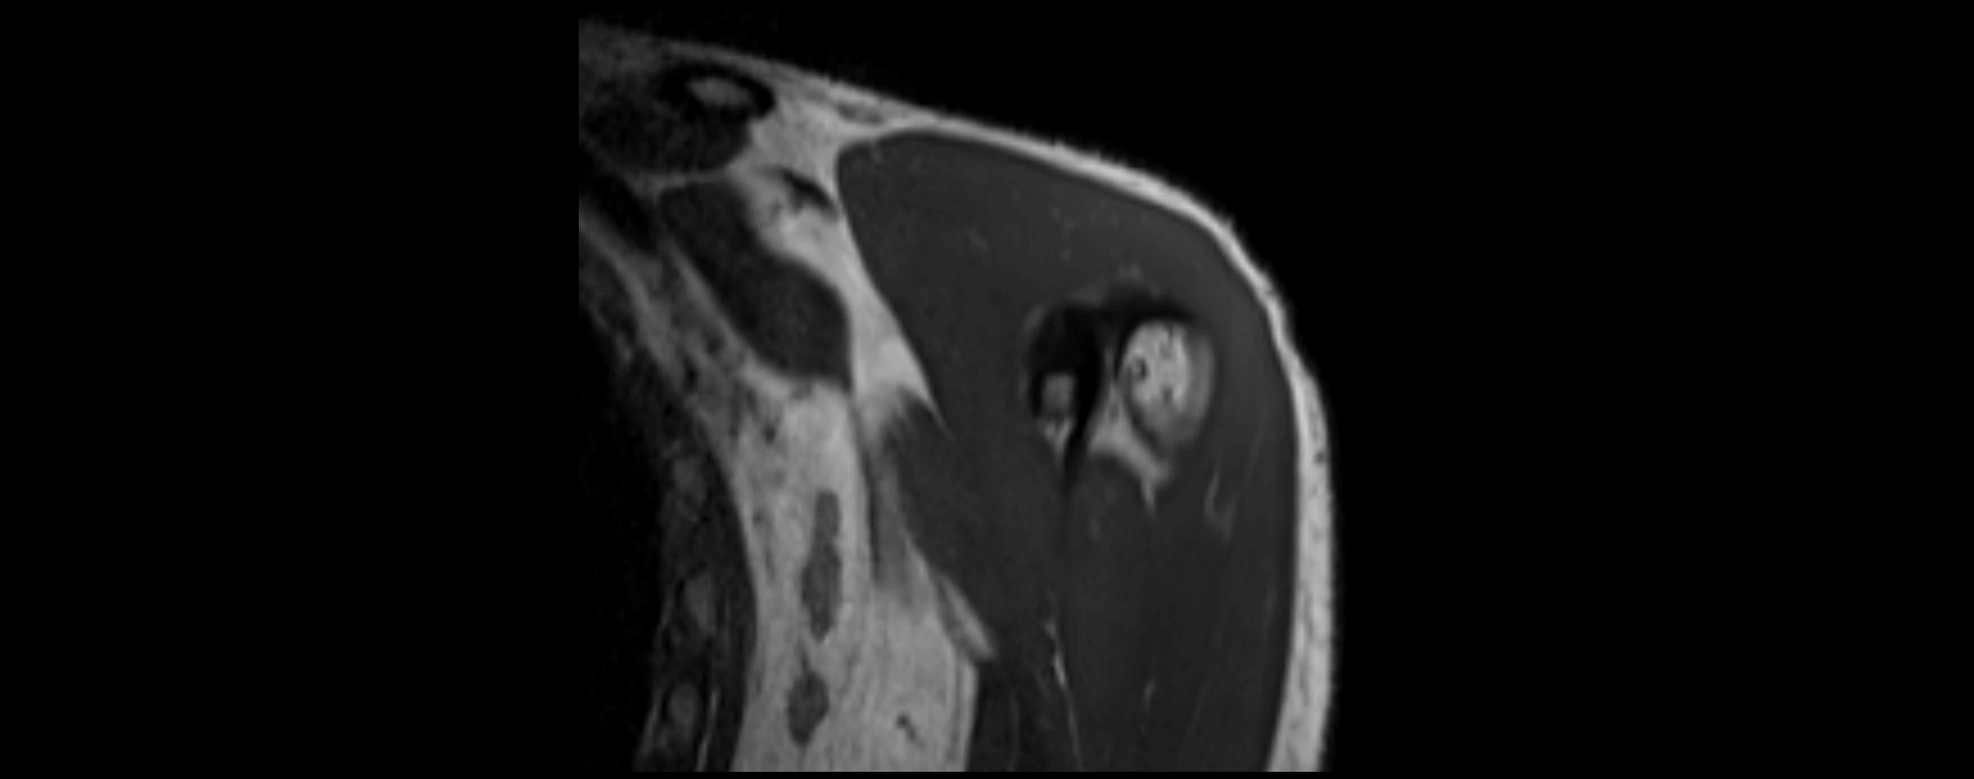

MRI images

image